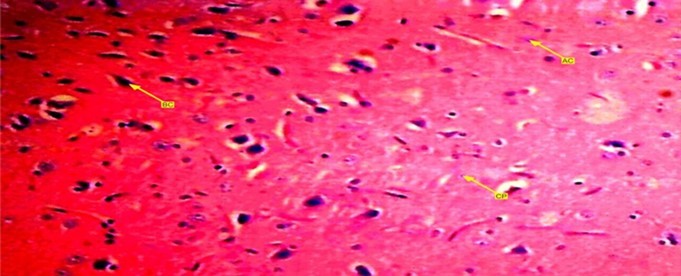

A buffered formalin bottled containing 10% solution was used and preserved the brain tissues of experimental wistar rats. Each bottle was labeled up and allowed to stand for 72 hours in order to ensure maximum penetration. After that, they were placed in ascending dehydration with ethanol solution. First 70% of ethanol solution was used for an hour then subsequent 95% solution and lastly alcohol solution for absolute dehydration. Tissue clearance took place in three (3) subsequent changes of xylene each lasting for 15 minutes. Tissue embedding with paraffin wax was carried out overnight to form blocks which were trimmed and sectioned at 5micro thickness using rotary microtome. Warm water at 28 degree Celsius bathed the tissue samples and dried up on an aluminum glass slides with heamotoxylin and eosin staining method which cleared up 95% of the xylene in alcohol and washed up in running tap water for 15 minutes. The differentiated section o turned blue after addition of 1% alcohol and eosin for 1 minute. The stained sections were viewed under a light microscope and photomicrographs of the stained tissues were taken. Figure 1, Figure 2, Figure 3

Figure 1.Showed a photomicrograph of anterior pituitary gland of female wister rat treated with progesterone pills for 72 days. It causes decrease in acidophilic and basophilic cells compared with control group. Chomophobes are also in less proportion compared with control group.